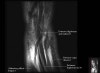

- Coronal section

Coronal T1 imaging evaluates bone marrow signal (ex. increased in avascular necrosis) and the relationship of the osseous structures to each other (ex. scapholunate disassociation).